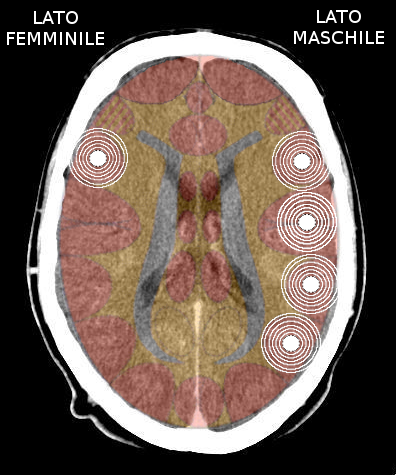

- Insula destra = ormonalità, percettività e comportamento maschile, sia nella femmina che nel maschio, destrimane o mancino. Quando attivata causa tonalità depressiva;

- Insula sinistra = ormonalità, percettività e comportamento femminile, sia nella femmina che nel maschio, destrimane o mancino. Quando attivata causa tonalità maniacale.

L'avvio di una attivazione territoriale, deprime l'ormonalità dell'emisfero colpito.

- Attivazione → lobo temporale destro = calo del testosterone (maschile); diminuisce il percepito maschile, la persona si deprime (perde aggressività);

- Attivazione → lobo temporale sinistro = calo dell'estrogeno (femminile); diminuisce il percepito femminile, la persona diventa maniacale (acquista aggressività).